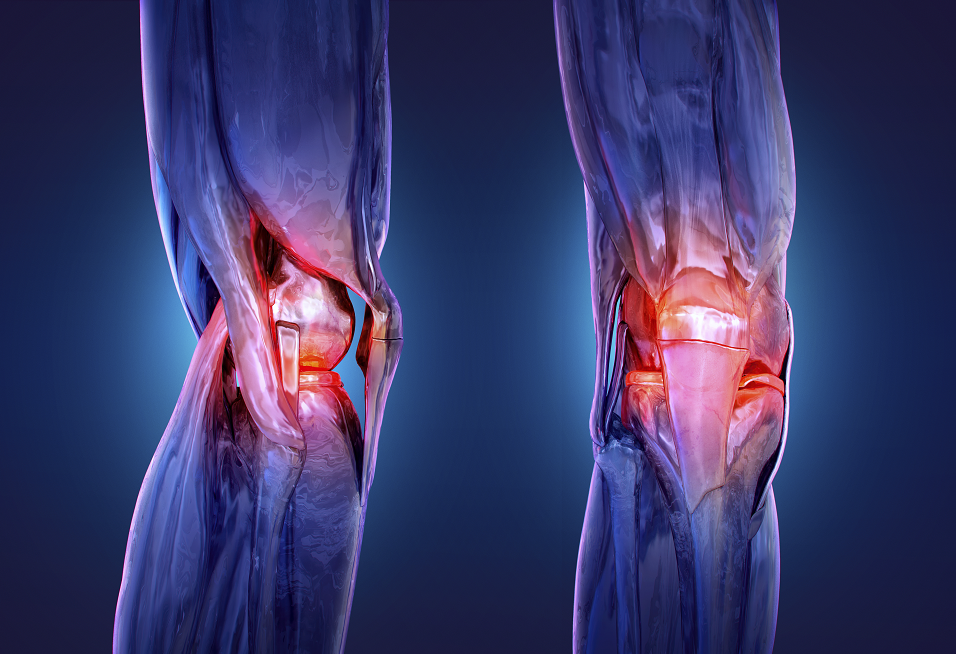

A new clinical study has shown that a single session of low-dose radiation therapy may provide a safe and effective option for patients with rheumatoid arthritis in the knee, especially in mild to moderate cases.

Researchers reported that patients who received this treatment noticed a significant reduction in pain and improvement in mobility over the following four months, noting that the doses used were much lower than those applied in cancer treatment. Since the study included a control group, the team was able to exclude the placebo effect, which is common in arthritis studies.

The trial involved 114 patients across three medical centers in South Korea, randomly assigned into three groups: the first received a very low dose (0.3 Gray – an international unit measuring absorbed radiation dose), the second a low dose (3 Gray), while the third underwent a sham procedure without radiation. All participants received six treatment sessions, with only paracetamol allowed for pain relief during follow-up.

After four months, 70% of patients in the 3 Gray group responded, compared to 42% in the control group, a difference described by researchers as “statistically significant.” More than half of the patients in this group showed clear improvement in pain and motor functions, with no radiation-related side effects observed.

Dr. Byung Hyuk Kim, the lead researcher from Seoul National University, said: “There is an urgent need for alternative treatments between mild painkillers and joint replacement surgery. Low-dose radiation therapy may represent this option, especially for patients who cannot tolerate medications or injections.”

Kim explained that the treatment might be more effective in patients whose joints still maintain their structure, while its benefit decreases in severe cases accompanied by advanced cartilage erosion.

The team plans to conduct longer follow-up studies up to 12 months, in addition to broader clinical trials and economic analyses comparing low-dose radiation therapy with injections and conventional drugs.

The preliminary results of the study will be presented at the annual meeting of the American Society for Radiation Oncology (ASTRO).